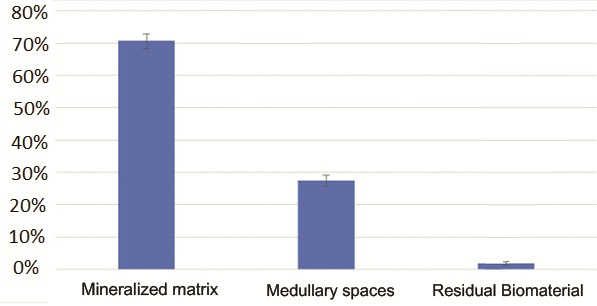

Гистологический анализ показал хорошо организованную, в основном зрелую ткань, образованную компактной пластинчатой костью с четко очерченными костными пластинками вокруг каналов Гаверсияна и Фолькмана, окруженных меньшими участками, в которых пластинки были менее организованными и богатыми остеоцитами на стадии созревания. Количество минеральной матрицы - от 69% до 72% - было особенно значительным. Воспалительного инфильтрата не наблюдалось.

Рис. 12 – Гистоморфометрическое исследование. Минерализованный костный матрикс занимает примерно 70% образца. Остаточный биоматериал составляет менее 2%.